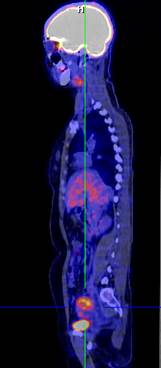

Hình 1. Bệnh nhân Nguyễn Th. H., nữ, 43 tuổi, chẩn đoán ung thư buồng trứng phải. Trên hình FDG-PET/CT thấy khối u buồng trứng phải tăng hấp thu FDG.